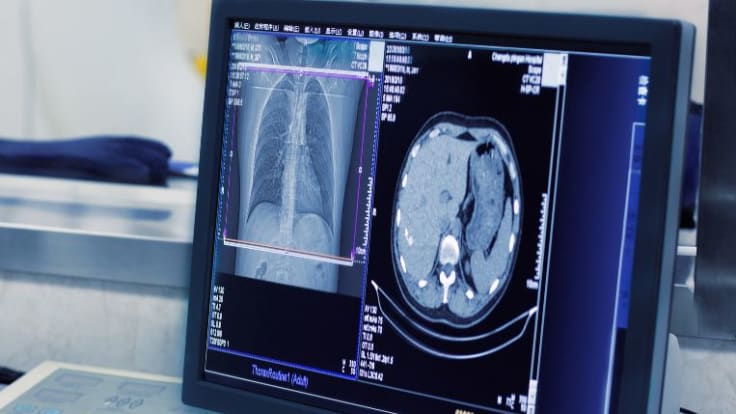

Radiographie et scanner sont deux techniques de radiologie utilisant les rayons X. La première est plus ancienne mais toujours aussi utile. La seconde est plus récente et offre des images en 3D.

Parmi ces techniques, l'on trouve la radiologie, technique la plus ancienne qui fait appel à des rayons X qui traversent le corps afin de produire une image en 2D de la zone du corps que l'on souhaite visualiser. Le scanner, technique plus récente, utilise aussi les rayons X mais propose des images en 3D. Pour passer un scanner on doit entrer dans une machine en forme d'anneau.

Le scanner, aussi appelé tomodensitométrie, est un appareil de radiologie qui offre la possibilité de voir le corps en deux ou trois dimensions. Les images qu'il propose sont très précises. Il utilise des rayons X. Le scanner se constitue d'un anneau ou d'un grand tube dans lequel le ou la patiente prend place. L'intérêt de cet appareil est de produire des coupes fines de la zone inspectée. Un produit de constraste peut être parfois nécessaire (il s'agit souvent d'un produit iodé).

Le scanner permet de visualiser le corps en 3D. Cela concerne toutes les parties du corps : organes, vaisseaux, os, articulations, moelle épinière... Il offre des coupes de l'organisme d'une grande précision. Le scanner permet de détecter de nombreuses anomalies qui ne sont pas visibles sur une radiographie ni une échographie, bien que certaines pathologies nécessitent des examens complémentaires comme l’IRM. Le scanner aide les professionnels de santé à vérifier si une tumeur est cancéreuse ou bénigne.